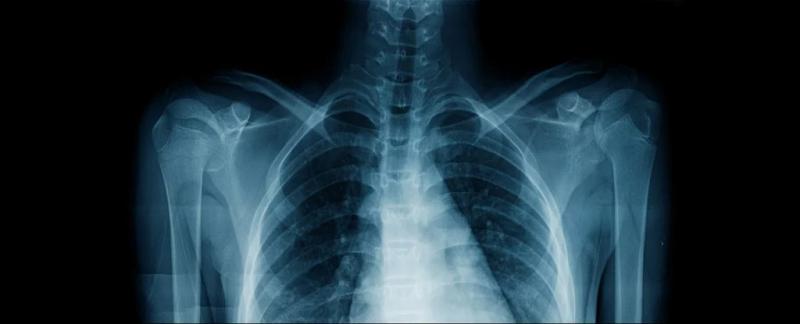

Модели глубокого обучения, основанные на искусственном интеллекте, могут определить расовую принадлежность человека только по его рентгеновским снимкам, показало новое исследование — то, что было бы невозможно для врача-человека, рассматривающего те же снимки.

Обучив свой ИИ на сотнях тысяч существующих рентгеновских снимков с подробным указанием расовой принадлежности пациента, международная группа исследователей в области здравоохранения из США, Канады и Тайваня протестировала свою систему на рентгеновских снимках, которые компьютерная программа не видела ранее (и не имела о них дополнительной информации).

ИИ смог предсказать расовую принадлежность пациента на этих снимках с удивительной точностью, даже если снимки были сделаны у людей одного возраста и одного пола. С некоторыми группами изображений система достигала уровня 90 процентов.

На данный момент ученые не знают, почему система ИИ так хорошо определяет расу по изображениям, которые не содержат такой информации, по крайней мере, на первый взгляд. Даже при предоставлении ограниченной информации, например, при удалении подсказок о плотности костей или сосредоточении внимания на небольшой части тела, модели все равно удивительно хорошо угадывали расу, указанную в файле.